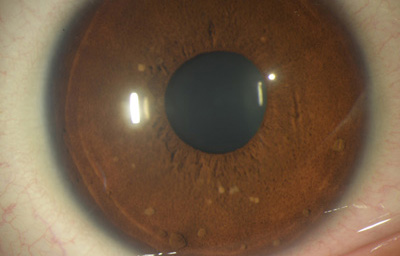

Nevus melanocítico en el Iris -“Nevus”

Estas lesiones que pueden ser pigmentadas o no, muestran más penetración en el estroma con distorsión, pudiendo producir ectrópion y corectópia. La célula névica es una variante del melanocito, son más grandes no tienen dendrítas y tienen un citoplasma granular mas abundante. En angiografía se aprecia que no tienen vascularización

Se considera que los adquiridos son neoplasmas benignos, mientras que los congénitos (perinatales) son considerados con un mayor riesgo de malignización.

Nevus melanociticos en el Iris

Archivo Fotográfico Dr. Francisco Barraquer

Nevus melanociticos en el Iris

Archivo Fotográfico Dr. Francisco Barraquer

Nevus con escaso pigmento

Archivo Fotográfico Dr. Francisco Barraquer

Se considera que los adquiridos son neoplasmas benignos, mientras que los congénitos (perinatales) son considerados con un mayor riesgo de malignización.

Son mas frecuentes en Iris claros, y su crecimiento o riesgo de malignización, esta relacionado con la edad siendo más frecuente en gente joven;